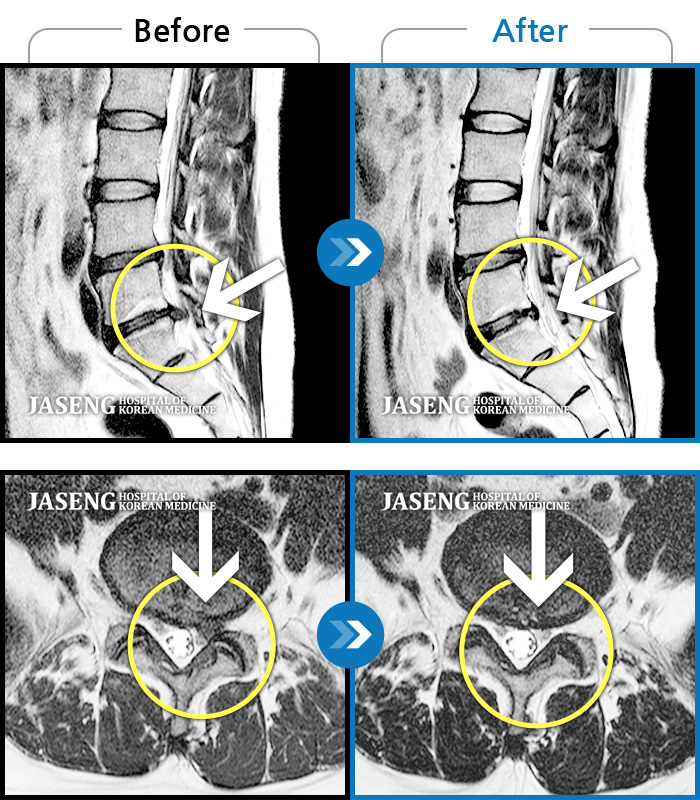

Before

After

환자에게 사전 동의를 받아 동일 조건에서 촬영되었습니다.

개인에 따라 치료 후 부작용이 발생할 수 있으니 의료진과 상담 후 치료를 진행하시기 바랍니다.

극심한 요통과 다리 통증으로 허리가 휘어진 채 내원

다리가 하루 종일 저려 제대로 걷지 못했다.